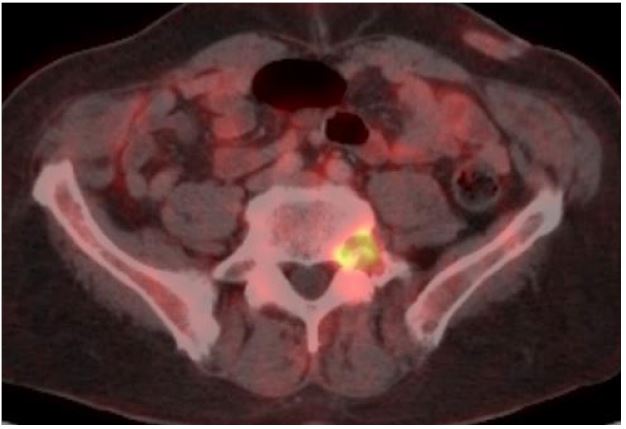

A 55-year-old man presented to an Internal Medicine physician after months of uncontrolled back pain despite of multiple therapies failure, asthenia, loss of weight and fever. Smoker, diagnosed of interstitial lung disease years ago, under follow-up by Pneumology and diagnostic doubts between bronchiolitis associated to tobacco smoking and pulmonary LCH, asymptomatic without specific treatment. Blood tests were unremarkable, with negative hepatitis serology and other infectious agents’ tests. Computer tomography of the chest showed centrilobular micronodules and cystic lesions in both lungs, with predilection for the mild and upper zones (Figure 1). These findings were consistent with the interstitial lung disease already known. A magnetic resonance of the spine showed multiple lytic bone lesions suggesting metastasis (Figure 2), so the study was completed with a PET scan that confirmed hypercaptation areas (Figure 3) in multiple vertebral bodies, scapula, pelvis, and costal arches.

Figure 2: Lytic bone lesions in spine RM.

Figure 3: PET TC with hypercaptation of a lytic lesion in L5.